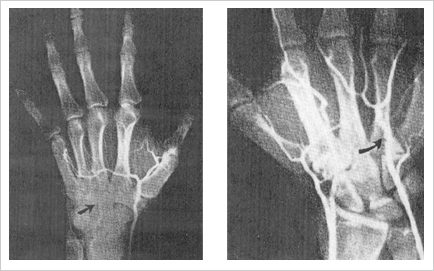

Hypothenar Hammer Syndrome

- Related to Judo, Karate, Cycling, Jackhammer usage similar activities to ulnar tunnel syndrome.

- Trauma to ulnar artery distal to Guyon's canal

- Pts present with digital ischemia, cold intolerance, pain in the palm

- Remember Allen's test